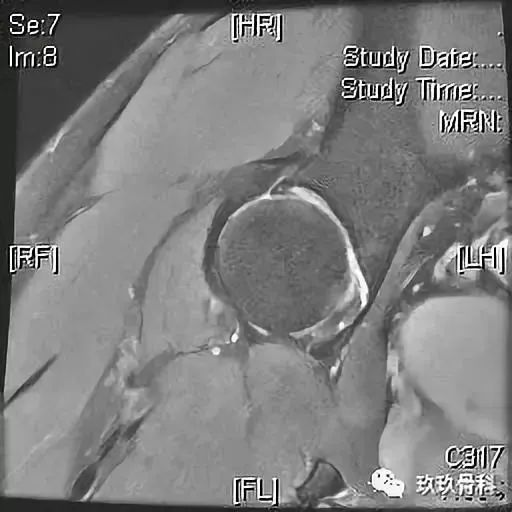

根据病情不同,术前检查有所不同,力求明确诊断。如果考虑髋关节撞击综合症,要做相应的特殊体位X片(骨盆正位+Dunn位),以及单髋盂唇核磁。不建议在当地医院检查,特殊体位检查需要有经验的医生和放射科医生合作才能完成,并且磁共振和CT这些检查档次也是不同的,在当地医院的检查只能作为参考。